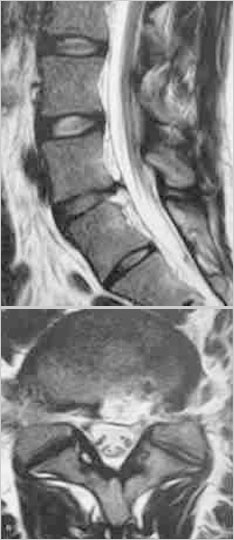

治疗后MRI

治疗后一个月后MRI